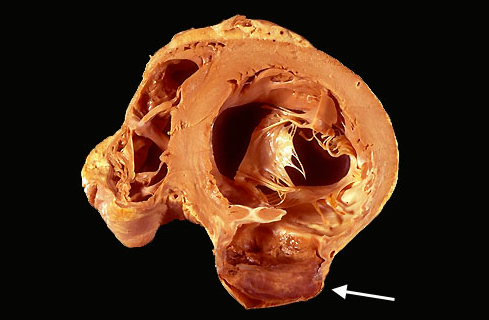

- A cross section through the heart reveals a ventricular aneurysm with a very thin wall at the arrow

- Note how the aneurysm bulges out

- The stasis in this aneurysm allows mural thrombus, which is present here, to form within the aneurysm